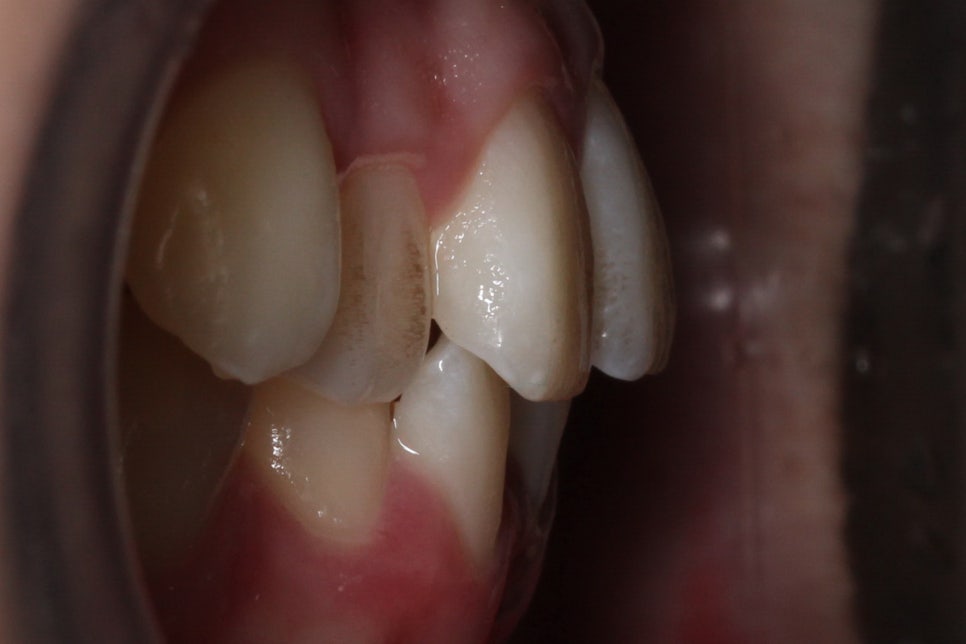

송곳니덧니 교정 전 상악의 치아 배열을 보면

전체적으로 좁고 긴 안모의 모습을 하고 있는데요,

순측으로 뻐드러져 있는 견치를 바른 각도로

조정하기 위해서 구치부 치아를 이동시켜

공간을 확보해야 할 것으로 보입니다.

아랫니의 경우 전치부의 총생이 심하고

삐뚤어진 부분에 치석과 치태가

쌓일 위험이 있기 때문에

바른 치아 배열을 중점적으로

비발치 클리피씨교정을 진행하였습니다.